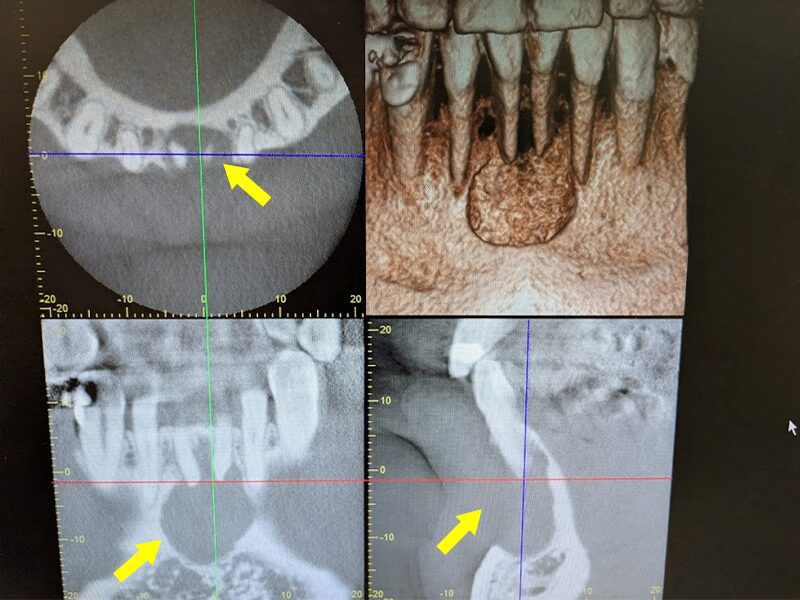

初診時のCT画像所見です。下顎前歯部の骨が大きく吸収していることが分かります。

術後1年経過しています。CT画像から骨の再生が起きていることが確認されました。特に頬側の皮質骨が再生しています。